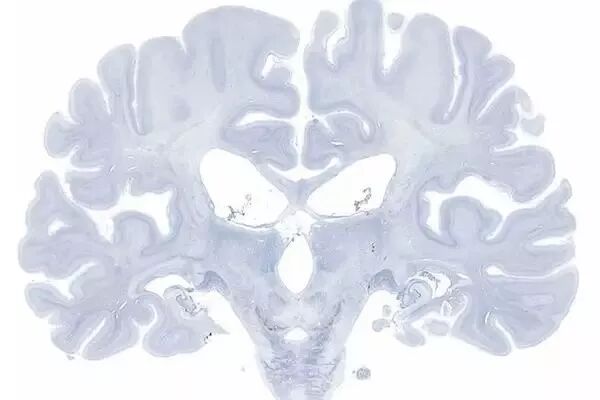

2009 年 12 月 4 日,H.M. 逝世一周年以后,他的大脑在加州大学圣地亚哥分校(UCSD)被制成了 2600 多个切片,每片厚 70 微米。这些切片至今保存在 UCSD,如同 H.M. 本人一样接受着一次又一次的测量和分析。亨利·莫莱森的大脑和爱因斯坦的大脑一样,成为了世界上被观测得最多的标本之一。

登录/注册后可看大图

H.M.大脑切片的尼氏染色